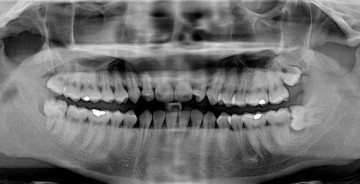

Это еще что. В начале прошлого века английский врач Уильям Хантер выдвинул идею, будто болезни — результат плохой гигиены полости рта, и лечение больного зуба не имеет смысла, все равно очаг инфекции не устранен. Поэтому в Европе и Америке при первом подозрении на кариес людям нещадно удаляли зубы, гланды и аденоиды. И несмотря на то, что в 1940 году теория фокального сепсиса была полностью опровергнута, советским детям еще долго вырезали гланды и аденоиды в целях «профилактики ангины», а потом… закармливали мороженым.